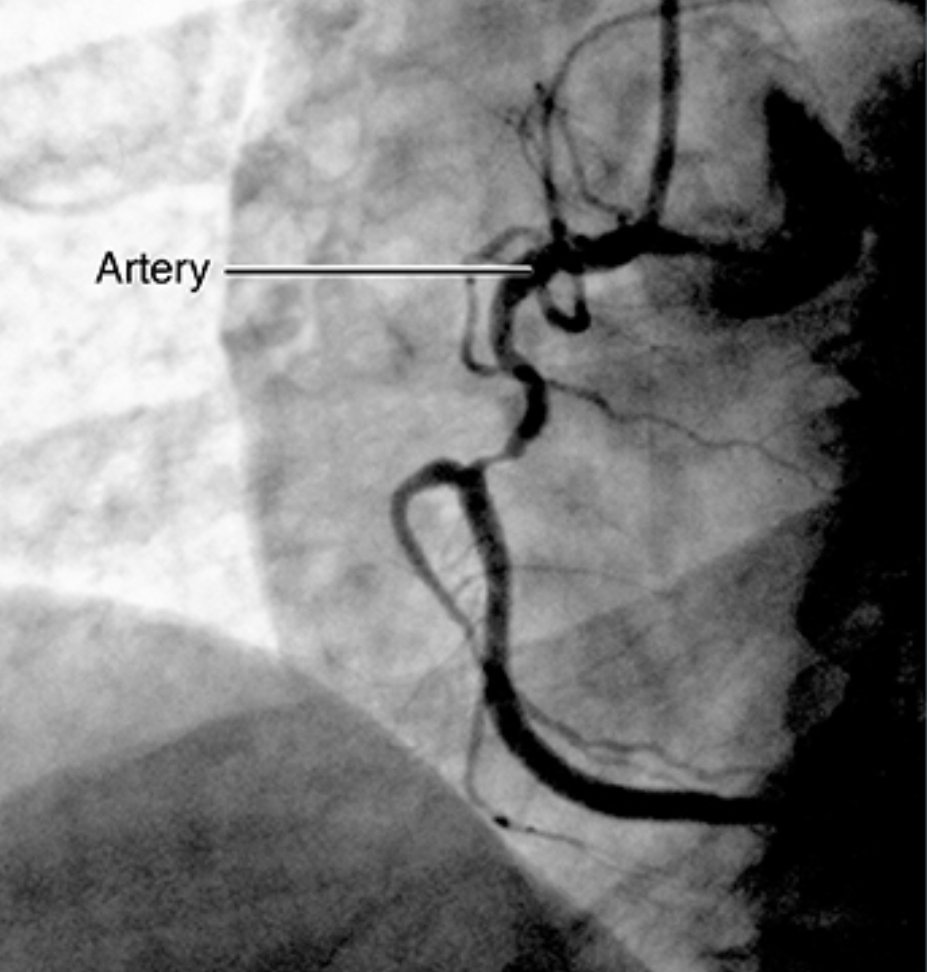

اما بالنسبة لمراكز القلب يقوم #طبيب التخدير بعمل #التخدير الواعي الاشعة فوق الصوتية للقلب عن طريق المرئ والصدمات وقسطرة القلب التشخيصية والعلاجية لشريايين القلب وقسطرة اصلاح او تبديل الصمامات و الصمامات الكهربائية لرجفان القلب عندما يكون المريض في وعيه